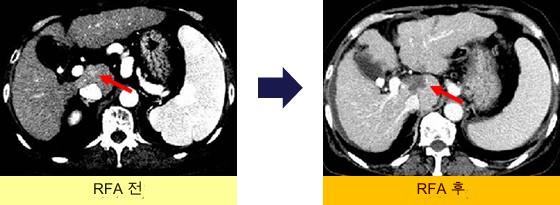

S1미상엽

S1 미상엽 병변.왼쪽 잎 바깥쪽부터의 어프로치로 RFA를 시행.재발 없음.